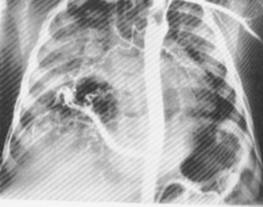

2. Sindromul de detresa respiratorie (boala membranelor hialine)

- este datorat unei deficiente (idiopatice) a surfactantului;

- in cazurile severe, radiologic se evidentiaza o aerare aproape absenta a plamanilor si prezenta de aer in bronhii (‘’ bronhograma aerica’’);

- in formele medii se observa opacitati reticulo-granulare in ambii plamani, datorate suprapunerii nodulilor acinari (cauzati de alveolele atelectaziate) si a bronhiilor dilatate.

Fig. 103 - Forma medie cu opacitati reticulo-granulare bilateral

Fig. 104 - Forma severa cu aerare diminuata si bronhograma aerica.